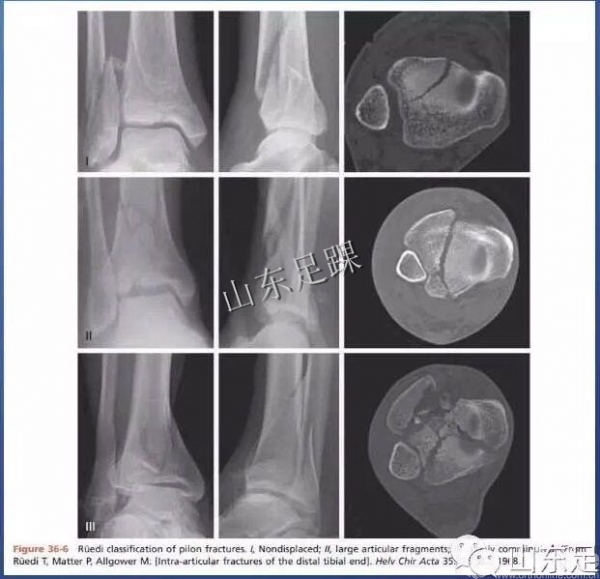

(2)胫骨Pilon骨折RÜedi-AllgÖwer分型

该分型以CT为基础,侧重描述胫骨远端关节面的粉碎程度,未涉及干骺端骨折的类型及受伤机制。

Ruedi-Allgower分型的缺点:不涉及损伤机制;几乎不包括干骺端、伴随骨折情况,过于笼统简单,难以指导治疗。